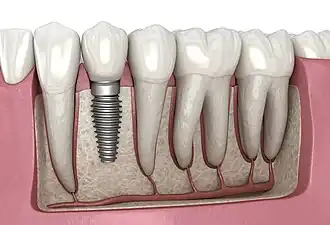

A dental implant (also known as an endosseous implant or fixture) is a prosthesis that interfaces with the bone of the jaw or skull to support a dental prosthesis such as a crown, bridge, denture, or facial prosthesis or to act as an orthodontic anchor. The basis for modern dental implants is a biological process called osseointegration, in which materials such as titanium or zirconia form an intimate bond to the bone.[1] The implant fixture is first placed so that it is likely to osseointegrate, then a dental prosthetic is added. A variable amount of healing time is required for osseointegration before either the dental prosthetic (a tooth, bridge, or denture) is attached to the implant or an abutment is placed which will hold a dental prosthetic or crown.

Single tooth implant restoration

Single tooth restorations are individual freestanding units not connected to other teeth or implants, used to replace missing individual teeth.[23] For individual tooth replacement, an implant abutment is first secured to the implant with an abutment screw. A crown (the dental prosthesis) is then connected to the abutment with dental cement, a small screw, or fused with the abutment as one piece during fabrication.[28]: 211–232 Dental implants, in the same way, can also be used to retain a multiple tooth dental prosthesis either in the form of a fixed bridge or removable dentures.

A typical conventional implant consists of a titanium screw (resembling a tooth root) with a roughened or smooth surface. The majority of dental implants are made of commercially pure titanium, which is available in four grades depending upon the amount of carbon, nitrogen, oxygen and iron contained.[35] Cold work hardened CP4 (maximum impurity limits of N .05 percent, C .10 percent, H .015 percent, Fe .50 percent, and O .40 percent) is the most commonly used titanium for implants. Grade 5 titanium, Titanium 6AL-4V (signifying the titanium alloy containing 6 percent aluminium and 4 percent vanadium alloy) is slightly harder than CP4 and used in the industry mostly for abutment screws and abutments.[36]: 284–285 Most modern dental implants also have a textured surface (through etching, anodic oxidation or various-media blasting) to increase the surface area and osseointegration potential of the implant.[37]: 55 If C.P. titanium or a titanium alloy has more than 85% titanium content, it will form a titanium-biocompatible titanium oxide surface layer or veneer that encloses the other metals, preventing them from contacting the bone.[38]